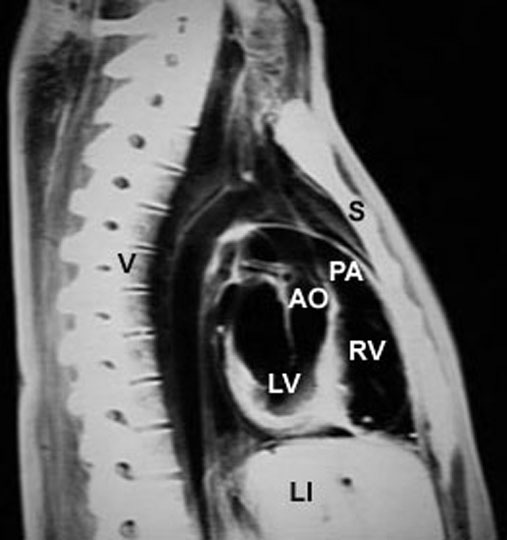

Posterior or left - interventricular septum